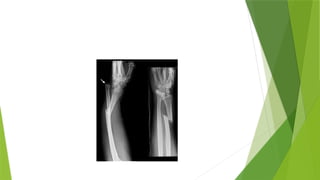

COLLES FRACTURE

 This is characterized by a transverse fracture of the radius just above the wrist with dorsal

displacement of the distal fragment.It is the most common of all fractures in older people

the high incidence being related to onset of postmenopausal osteoporosis.Thus the pt usually

an older woman who give a history of falling on an outstretched hand

 MOA;Force is applied in the length of the forearm with the wrist in extension.Then bone

fractures at the cortico-cancellous junction and the distal fragment collapses into dorsal

replacement, Radial tilt and shortening

 CLINICAL FEATURES; DINNER FORK DEFORMITY with prominence on the back of the wrist and

a depression in front. In pts with with less deformity there may only be local tenderness and

pain on wrist movements

 XRAY;TRANSVERSE FRACTURE OF THE RADIUS AT THE CORTICO-CANCELLOUS JUNCTION ABOUT

2.5cm above the wrist through the epiphysis

COLLES FRACTURE  Thisis characterized by a transverse fracture of the radius just above the wrist with dorsal displacement of the distal fragment.It is the most common of all fractures in older people the high incidence being related to onset of postmenopausal osteoporosis.Thus the pt usually an older woman who give a history of falling on an outstretched hand  MOA;Force is applied in the length of the forearm with the wrist in extension.Then bone fractures at the cortico-cancellous junction and the distal fragment collapses into dorsal replacement, Radial tilt and shortening  CLINICAL FEATURES; DINNER FORK DEFORMITY with prominence on the back of the wrist and a depression in front. In pts with with less deformity there may only be local tenderness and pain on wrist movements  XRAY;TRANSVERSE FRACTURE OF THE RADIUS AT THE CORTICO-CANCELLOUS JUNCTION ABOUT 2.5cm above the wrist through the epiphysis